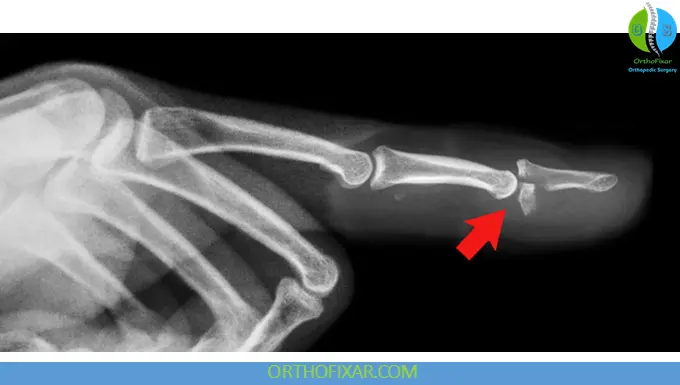

- Type III: Avulsion with bony fragment

- X-rays: Detect bony avulsion fragments